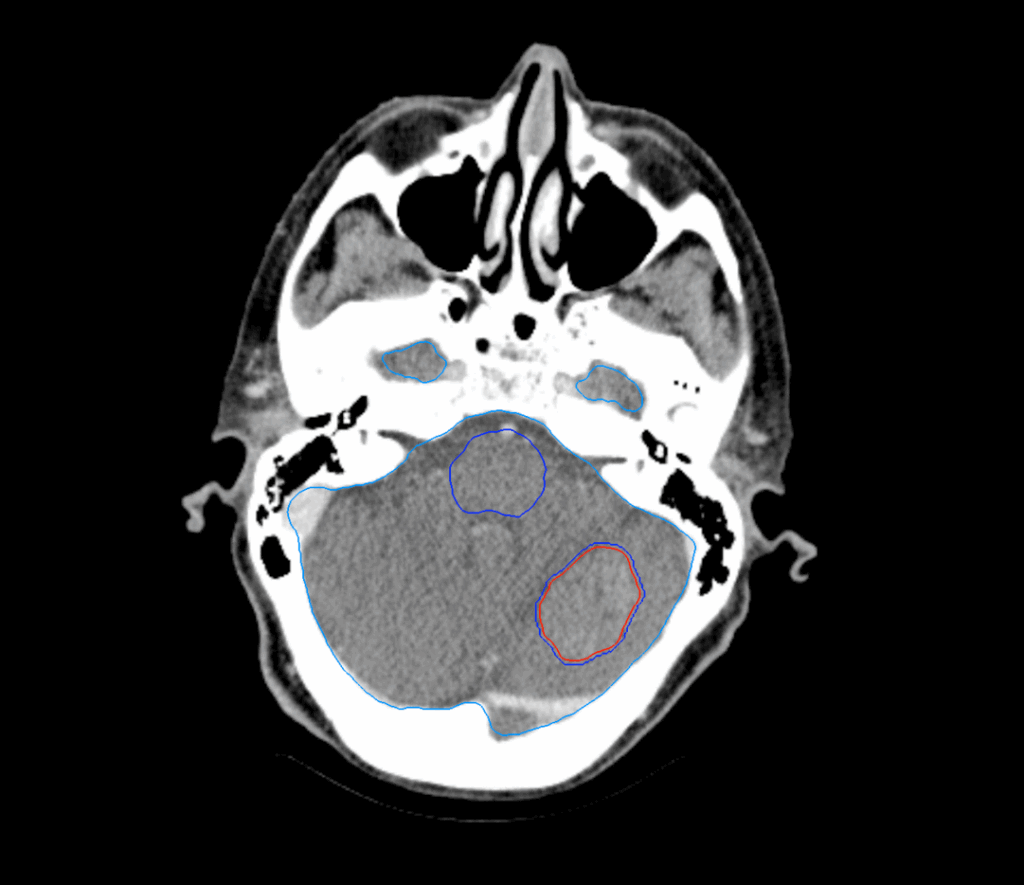

Planning CT Images

MRI: metastasis in the cerebellum, measuring 3.2cm